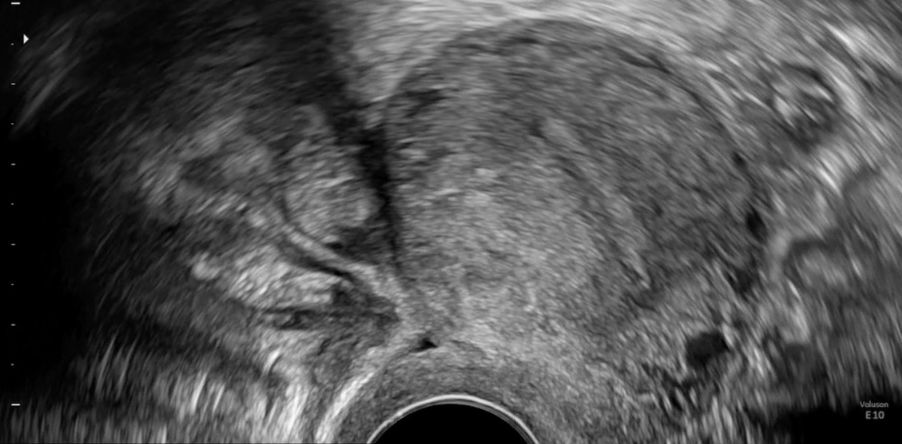

Endometriosis may present as nodules or adhesions. Adhesions stick together organs like the uterus, ovaries, and bowel. These are very difficult to detect but have to be diagnosed when mapping the individual spread of endometriosis. At Scanvio we are establishing a new medical standard for ultrasound-based diagnosis of endometriosis which will be directly implemented into our product.

In general, ultrasound data is much more difficult for machine learning models to interpret than, for example, CT or MRI data. Due to the free-hand motion, sonography is a very dynamic examination. Furthermore, the produced images are very noisy, which makes reading them challenging for both the operator and the algorithm.